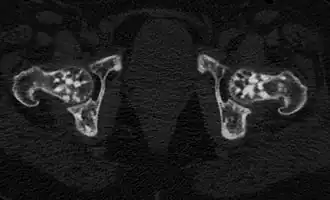

Проявления остеопойкилии в костях таза и головках бедренных костей (компьютерная томограмма). | |

Остеопойкилия (остеопойкилоз, остеопатия врождённая пятнистая множественная, остеопатия врождённая рассеянная склерозирующая) — редкое наследственное заболевание костной ткани, проявляющееся в негомогенности, «пятнистости» её окостенения.

Заболевание является системным, проявляется очагами остеосклероза округлой и овальной формы, как правило приблизительно одинакового калибра, от 2 мм до 20 мм. Очаги могут располагаться практически во всех костях, однако наиболее часто выявляются в коротких костях запястья и предплюсны, метафизах и эпифизах длинных трубчатых костей (плечевых, бедренных) при интактности их диафизов[6].

По характеру морфологических проявлений различают пятнистую, полосатую и смешанную формы заболевания[6].